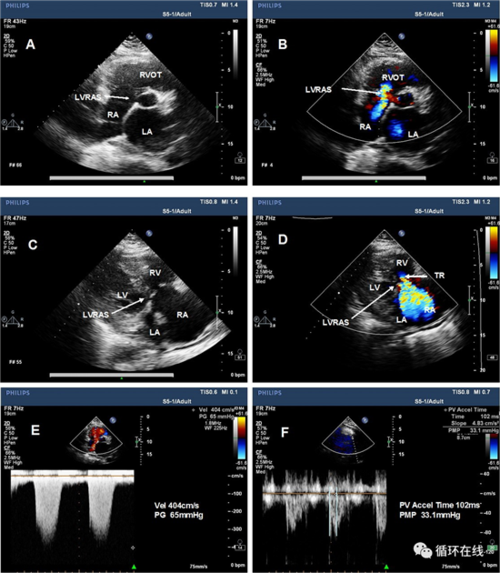

1左室右房分流的超声心动图特征